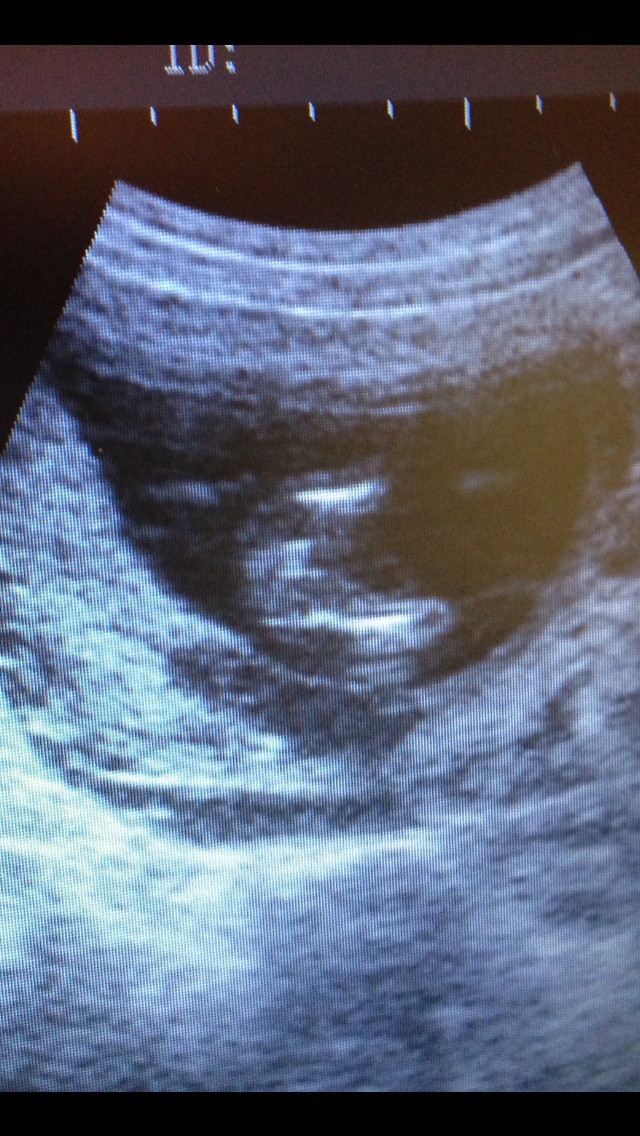

Hi these were taken at 15 weeks 1 day what gender do you think pleaseAttachment 13623

Potty shotAttachment 13625

i think girl x nub is straight in line with spine and potty view has those triangle lines famiilar to girl, head is very roundish too x